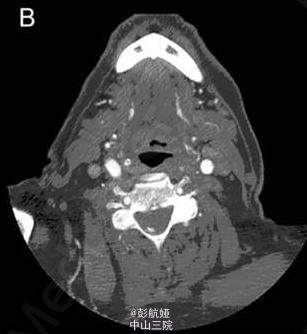

头颅血管造影(CTA)结果(如图 1 所示)示颈椎管可见斑点征和高密度影。 进一步完善 MRI 证实为 C4-T1 的硬膜外血肿(如图 2 所示)